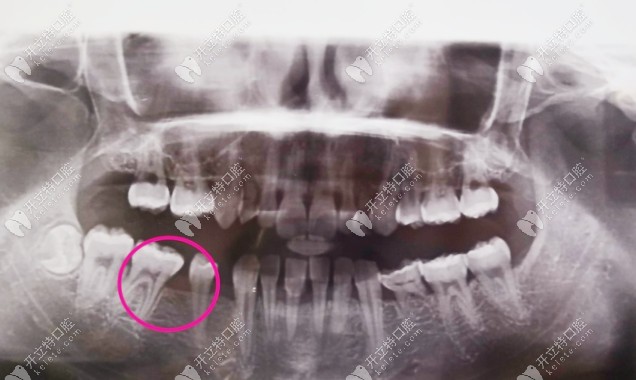

這是我到牙科拍的片子,大家應(yīng)該能看出來(lái)掉了兩顆吧,牙齒很不好,還有牙結(jié)石▼

牙齒拍片子的照片

醫(yī)生告訴我一顆牙齒的空隙已經(jīng)沒(méi)有辦法再安上一顆牙了,種植牙對(duì)于我來(lái)說(shuō)確實(shí)分擔(dān)不了,所以就考慮了全瓷牙,靠近兩側(cè)的牙戴烤瓷牙套把縫填上。